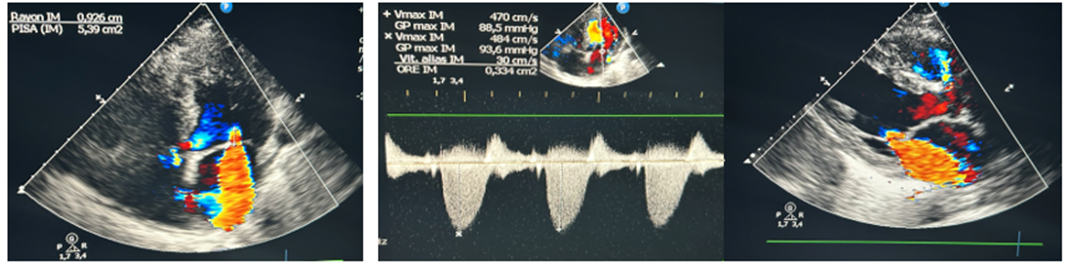

Figure 5: This 77-year-old patient was admitted with post-MI angina in inferior position, extended to the right shunts at H24, complicated by cardiogenic PAO. Echocardiography showed acute mitral insufficiency, on segmental hypokinetic cardiopathy with severe 30-35% LV dysfunction.